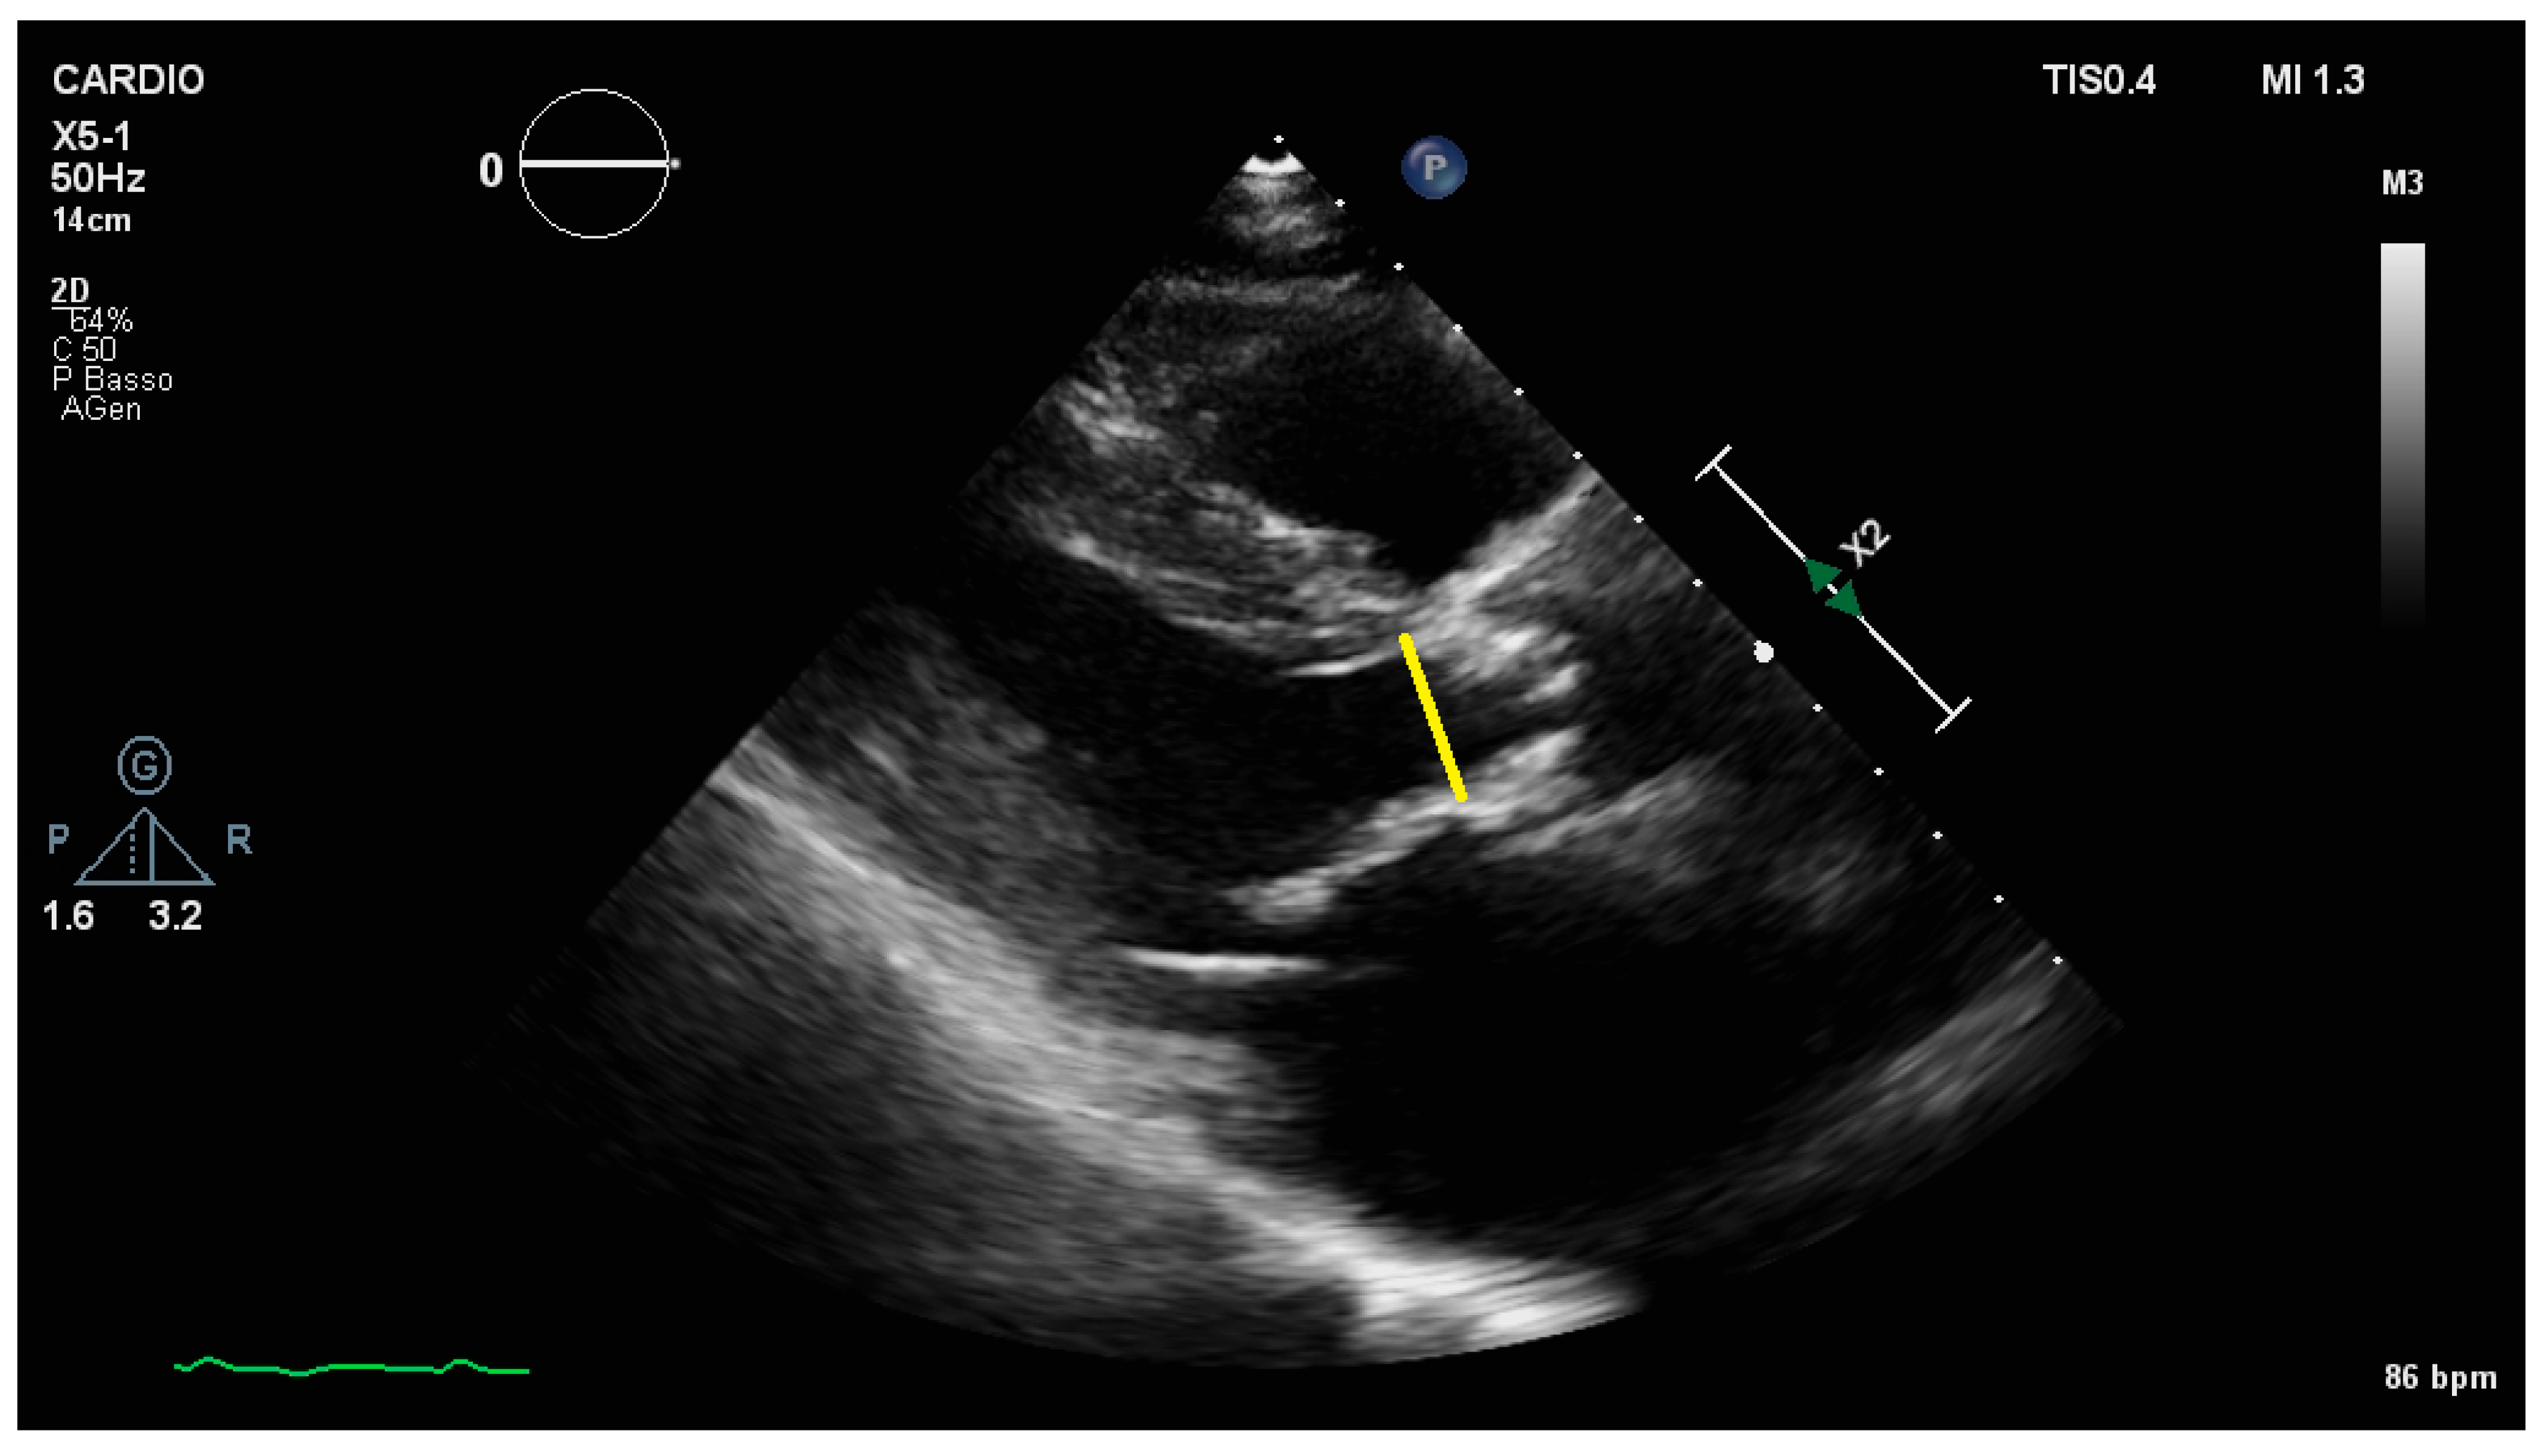

2.2. Aortic Valve Area